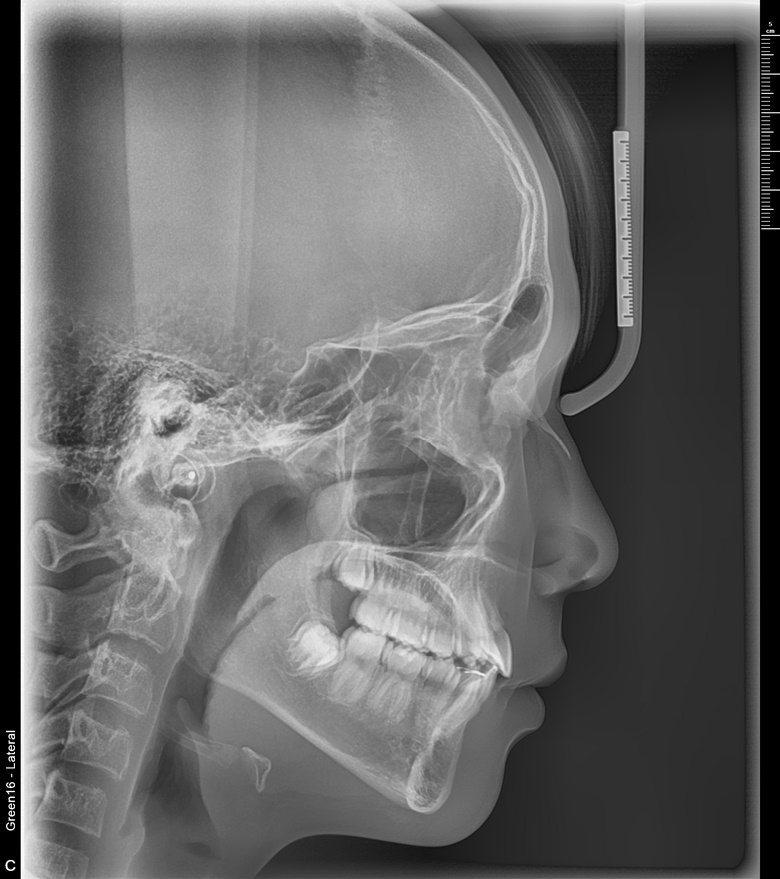

치료 전 사진입니다.